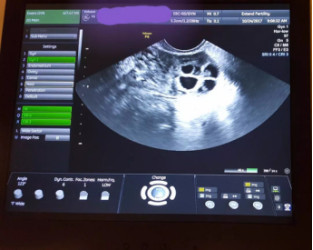

在医生的专业指导下,我进行了前期验血,阴超以及常规体检,结果令人格外惊喜

就这样,我正式开启了自己的冻卵之旅。我从来没有如此频繁地去医院,早上检查FSH、EZ和卵泡发育等指标,晚上按照医生要求打针,这也是我第一次拿起了注射器

经过十多天的促排,我的卵泡长到了18mm。我躺在了取卵的手术台上,在麻醉药的作用下,我渐渐失去了意识。迷迷糊糊中,我梦到躺在一片漂亮的花海中,身边还有一个非常可爱的baby

当我清醒时,医生温柔地注视着我,告诉我顺利取出了9颗卵子。一系列精细操作后,我的卵子由温暖的卵巢被封入零下196℃的冰冻世界里